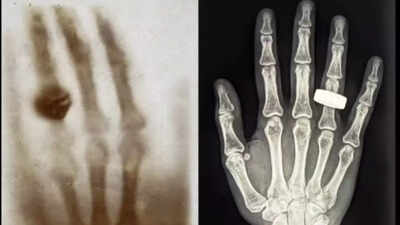

In 1895, a German professor of physics named Wilhelm Röntgen was experimenting with cathode rays when he stumbled upon an unintentional discovery that will remodel the sphere of medical science. While finishing up experiments, he seen an odd glow in a fluorescent display in his laboratory. This resulted in the identification of a brand new kind of radiation, which he dubbed “X-rays” due to their unknown character. Recognising the medical makes use of of this expertise, Röntgen rapidly took the world’s first X-ray picture of the human physique. The legendary {photograph} was that of his spouse’s hand, which wore a hoop, the beginning of a brand new age in diagnostic drugs.

The Fram2 mission took three and a half days, throughout which 22 analysis experiments have been carried out by the crew. These assessments various from viewing Earth’s poles and finishing up organic analysis, like cultivating mushrooms, to extra scientific pursuits, like making X-ray photographs of the human physique in space. The first X-ray picture taken by the crew was of a hand, much like Röntgen’s first picture, however this time taken in the particular situations of space. This take a look at was the primary time that X-ray imaging had been employed on a human physique whereas in space.